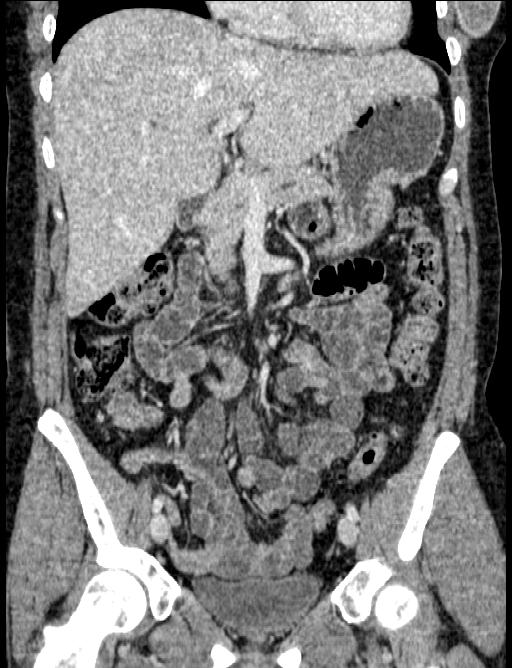

2009